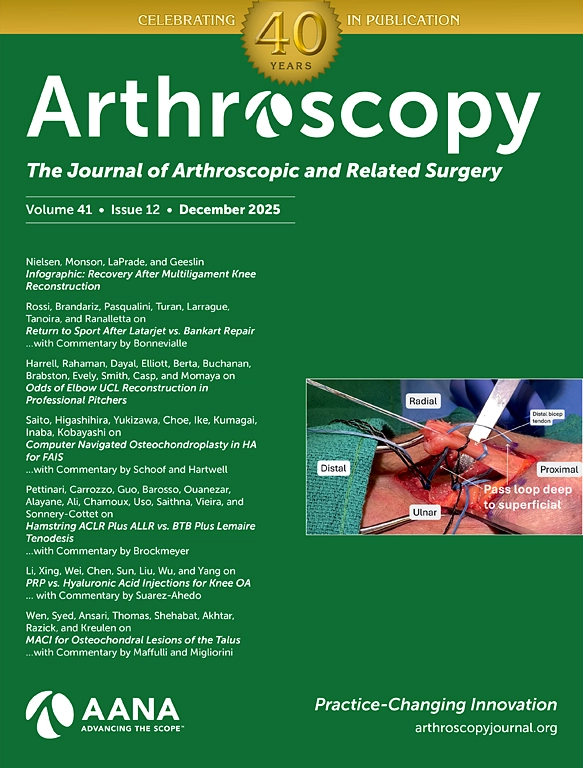

- BS Papers

Planejamento Cirúrgico Personalizado para Prótese e Osteotomia

Conte com uma análise especializada para planejar cirurgias de prótese e osteotomia com mais precisão e previsibilidade.

- Videocast

Aqui você encontra highlights de congressos mundo afora e discussões de artigos com nossos especialistas